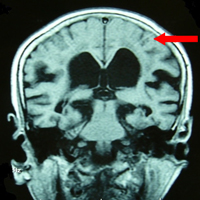

診断

診断はまずは特長的な痛みを備えているかということを問診で確認します。次にMRIを用いて三叉神経周囲を細かく調べます。

原因

原因の90%以上は神経に対し血管が圧迫することです。

三叉神経痛の治療法として薬物治療、神経ブロック、放射線治療、手術があります。手術は神経を圧迫する血管を移動させるというもので根本的な治療といえます。

手術は微小血管減圧術といいます。耳の後ろを5cm切開し、頭蓋骨に500円玉程度の穴をあけます。この時髪の毛はほんの少しだけ剃るのみです。ここから手術用顕微鏡を用いて圧迫血管を移動させます。手術時間は1時間20分、全身麻酔で行い、手術翌日から自由に動くことができます。入院期間は10日程度です。本手術の合併症として難聴が挙げられますが、予防のために手術中、聴性脳幹反応を持続的に確認しながら手術を進め、難聴を防いでいます。